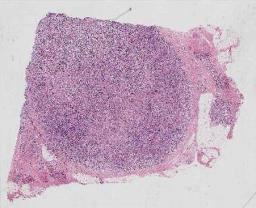

临床资料: 患者,男,67岁主诉:发现淋巴结肿大5月余入院,当地医院行B超提示:右侧腹股沟区淋巴结肿大,大小约5.3*1.6cm,部分淋巴门结构欠清。予以口服消炎药(具体不详),自觉淋巴结稍缩小,后未再复查及治疗。近期自觉颈部淋巴结增大,否认发热、乏力、盗汗等不适,遂至我院门诊就诊。发病以来,神志清,精神可,饮食可,睡眠欠佳,大小便如常,体重、体力无明显变化。

大体所见: 右颈部淋巴结(切片链接:https://zyd.winmedic.cn/#/share?sid=MjMzOA==)(复制网址并粘贴至浏览器地址栏打开)